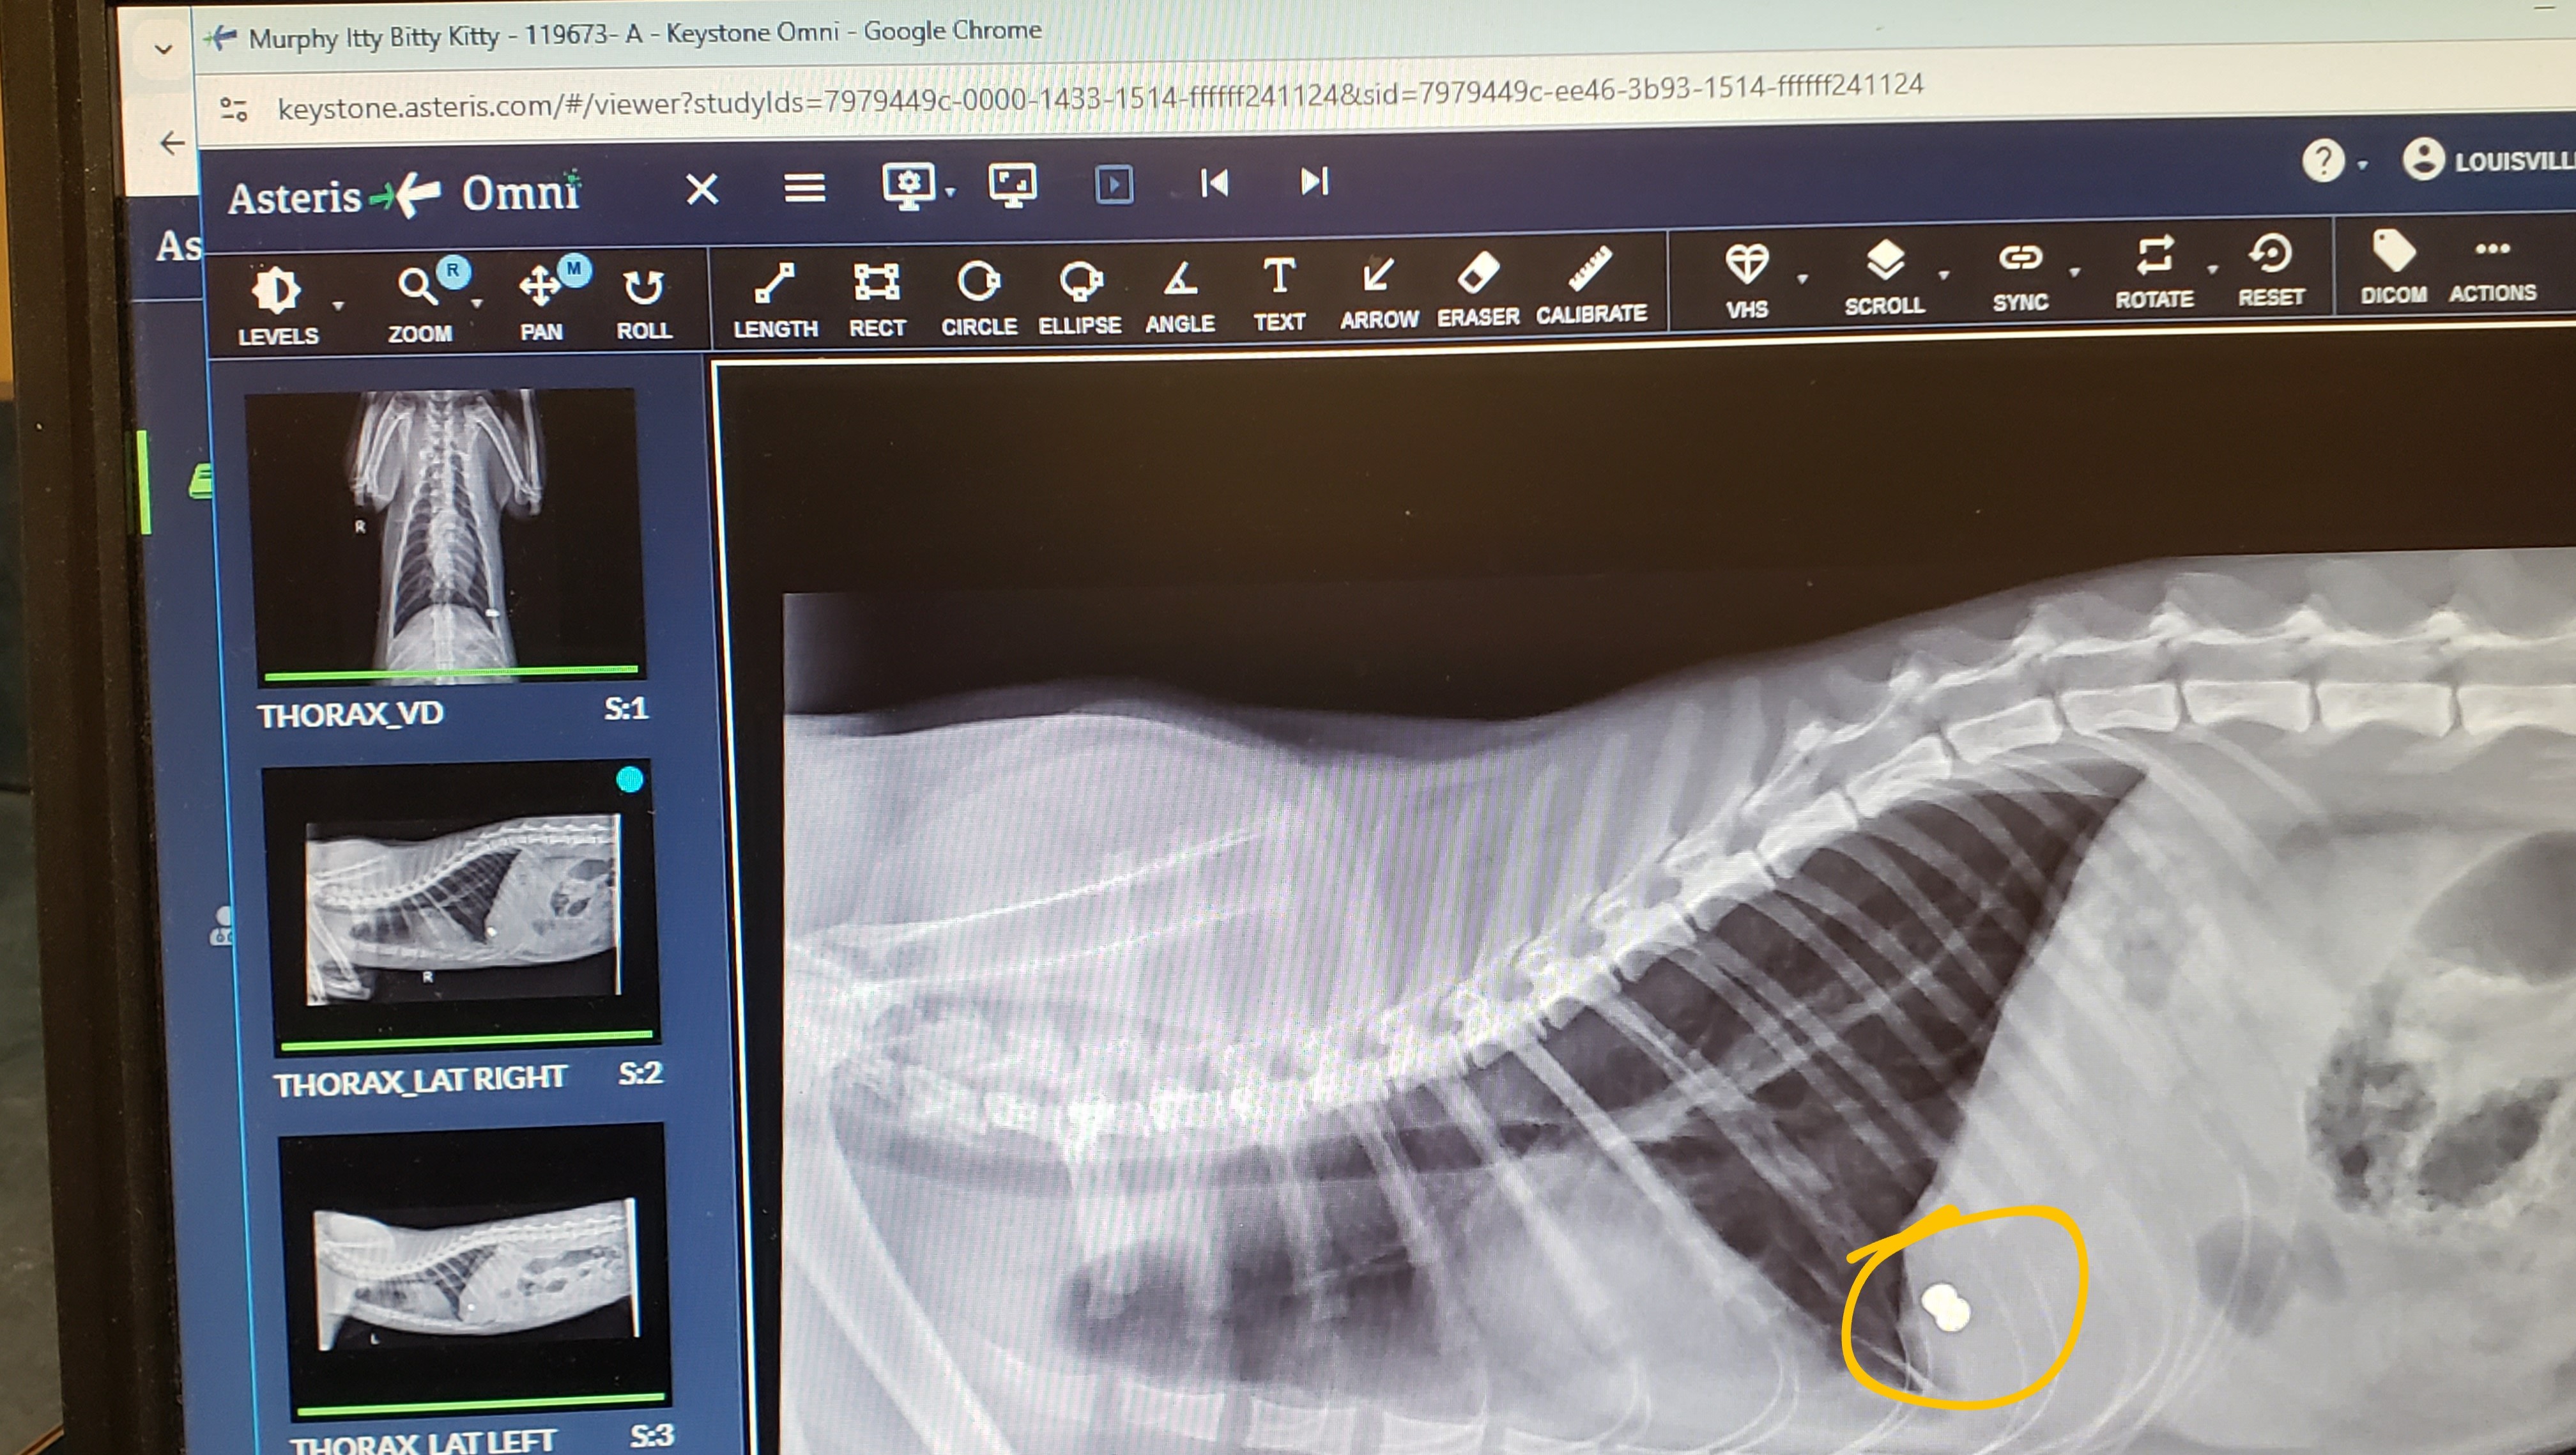

My cat came home that morning bleeding profusely from a wound on his side. When I couldn't get the bleeding to stop, I rushed him to the emergency animal hospital in Louisville. They cleaned the wound, took an x-ray, gave him a shot of antibiotics, and applied some pain medicine. $1200 later, I was informed that it appeared as tho he was targeted by someone that clearly intended to kill him (because of the type of ammunition used), but that he was "very lucky" because it missed his heart and his lungs. Which got me thinking: I have another cat that went missing on November 2nd, which is highly unlike her to not come home; what are the odds that something unrelated happened to both of my cats only a few weeks apart? I feel that it is highly unlikely for that to be the case. What I think happened, is that my other cat wasn't so "lucky", which breaks my heart to think about. Why would someone target my cats with the intention to kill them?! If they were bothering you somehow, why not come talk to me about it? Whatever happened to being "neighborly"?